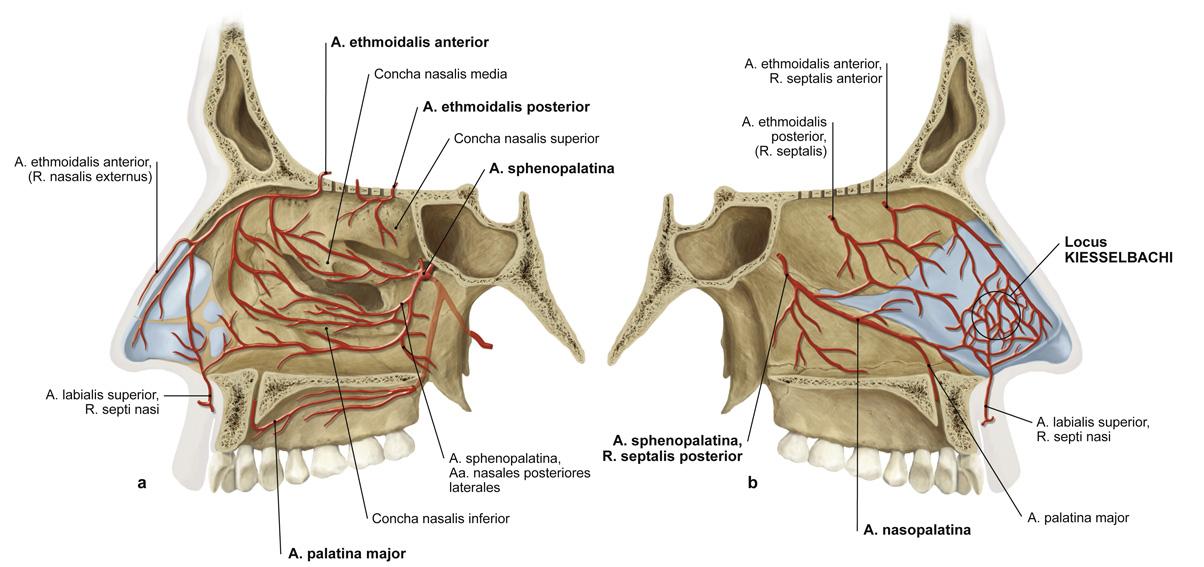

Fig 3.10b: a. maxillaris - sfenomaxillair deel - neusholte

|

|